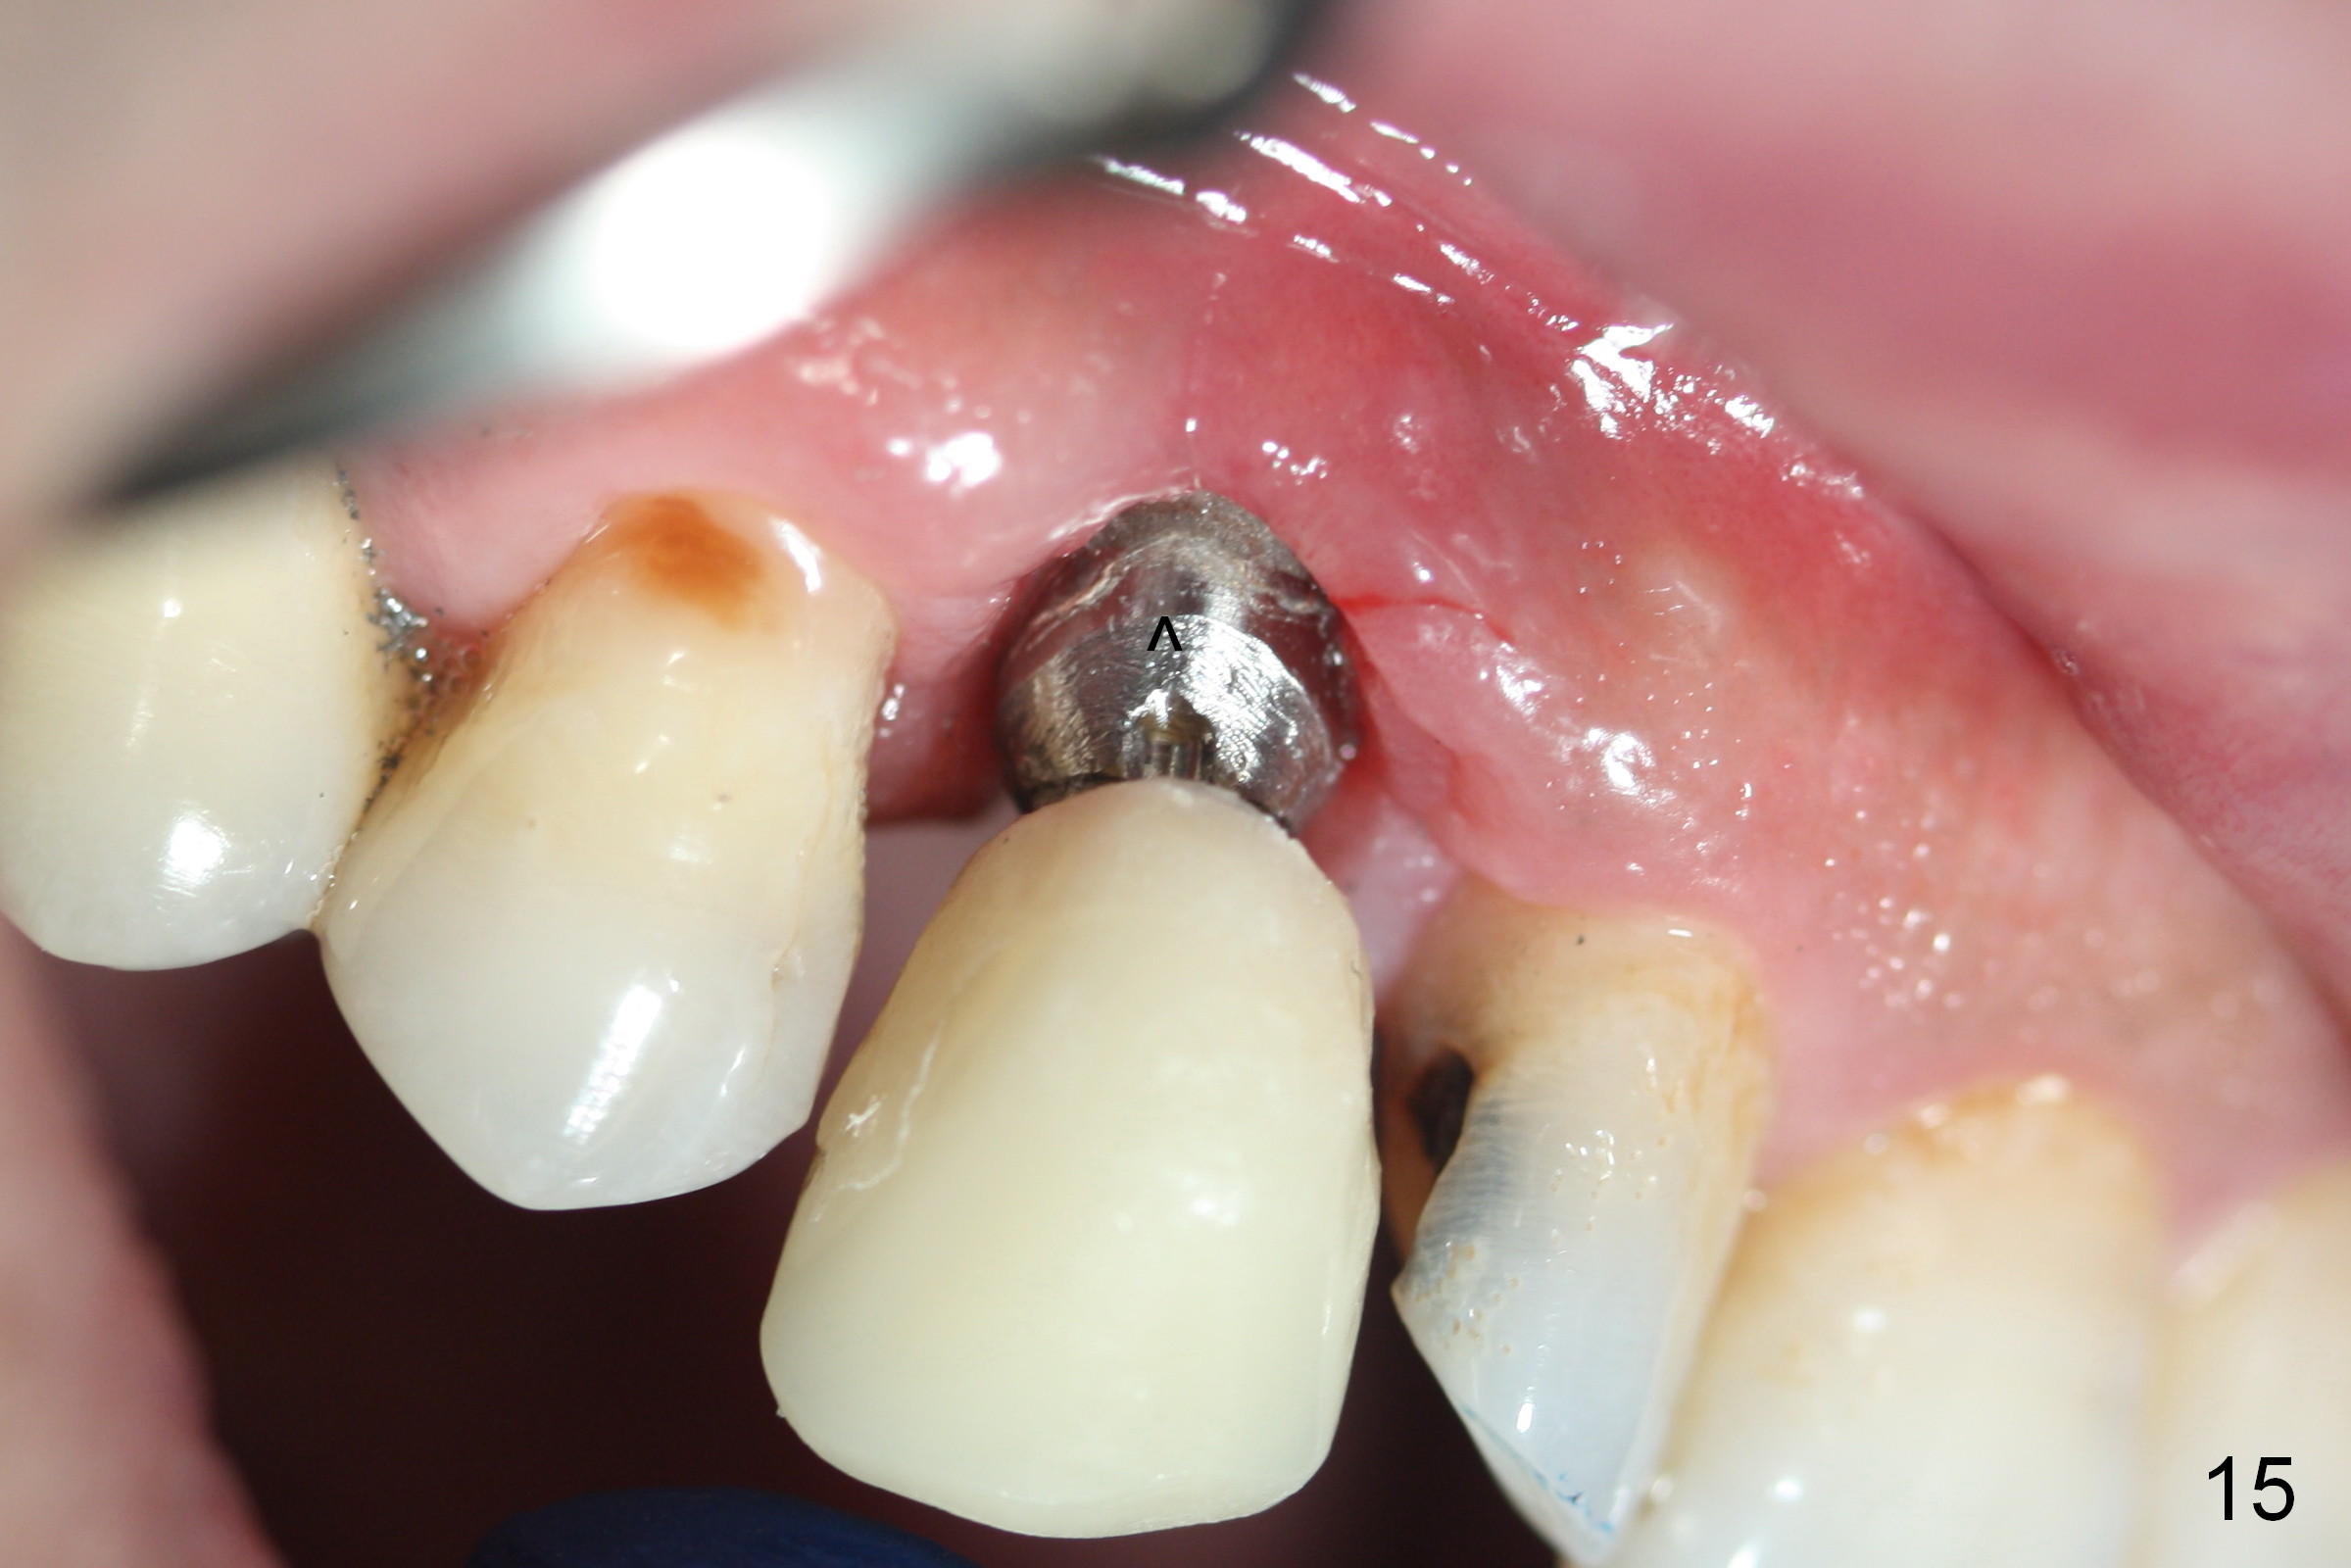

The patient returns 1.5 months postop. The provisional margin is much higher than that of the neighboring teeth (Fig.12,13: #6), unlike the opposite side (Fig.12: #11). When the provisional is removed, the implant margin is at the same level as that of the neighboring teeth (Fig.14 arrowheads). The implant margin is slightly extended apically (Fig.15 ^) prior to seating of the modified provisional. When the provisional is seated, its margin (Fig.16 ^) is at the implant margin; the gingival margin (*) is free and expected to move coronally by itself.